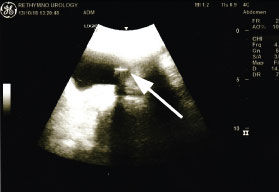

A 42-year-old woman presented to the emergency department claiming accidental foreign body insertion into her bladder. The patient had a history of self-intermittent catheterization over the past 10 years due to neurogenic bladder related to multiple sclerosis. She claimed that during her last catheterization she accidentally pushed the catheter inside her urethra because she confounded it with her vagina tampon. The ultrasound evaluation confirmed the foreign body inside her bladder (Figure 1). Eventually, the 12Fr hydrophilic single-use catheter was removed under cystoscopic direct vision, after grasping the tip and pulled out through the urethra (Figure 2).

Figure 1: Sagittal ultrasonographic plane of the patient's bladder. The foreign body creates the characteristic acoustic shadow (white arrow).